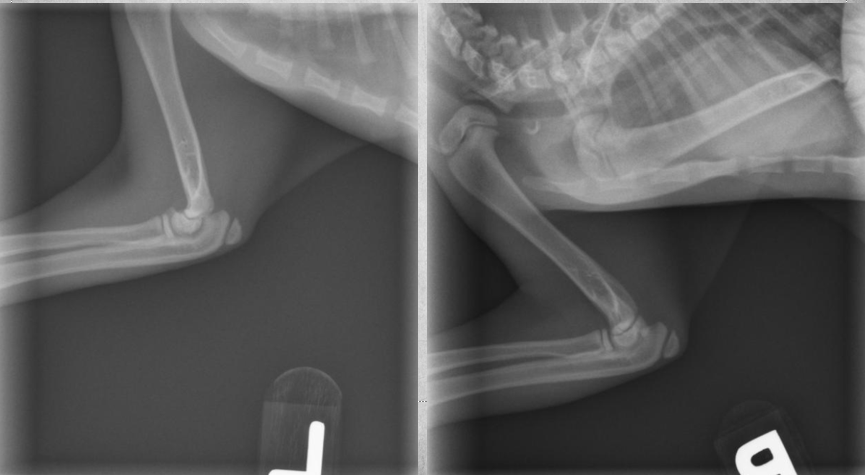

4 months old male kitten

Not using left front leg

A

diffuse soft tissue swelling of the left forelimb. The physis of the distal radius has a thin radiolucent line just proximal to it.

7

Q

4 months old male kitten. presenting complaint Not using left front leg.

images from 4 weeks later:

4 weeks later: The soft tissue swelling is decreased.

Both proximal and distal growth plates of the radius are closed.

There is well defined new bone formation, especially at the proximal diaphysis of the radius.